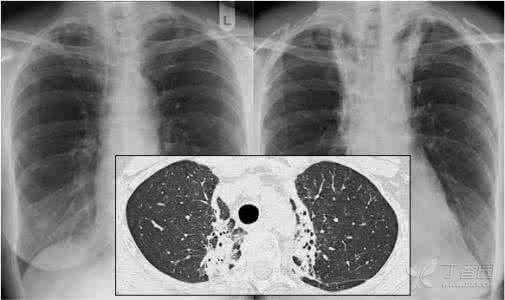

放射性肺炎的病理变化可分为急性放射性炎症改变和慢性纤维化病变,急性炎症改变多发生在放射治疗后1~2个月,亦可发生在放射治疗结束后6个月,主要表现为肺毛细血管,小动脉充血,扩张和栓塞,血管通透性增高,肺泡细胞肿胀。

Ⅱ型肺泡细胞和肺泡巨噬细胞增加,淋巴管扩张和肺泡内透明膜形成,肺泡壁有淋巴细胞浸润,急性可自行消散,也可有结缔组织增生和纤维化,慢性阶段的肺组织变化为广泛肺泡纤维化,肺泡间隔增厚,肺泡萎缩,血管内壁增厚,玻璃样变和硬化,管腔狭窄或阻塞致使气体交换功能降低和肺动脉压力增高,若继发肺部感染可促进放射性肺纤维化,也是导致死亡的重要诱因。